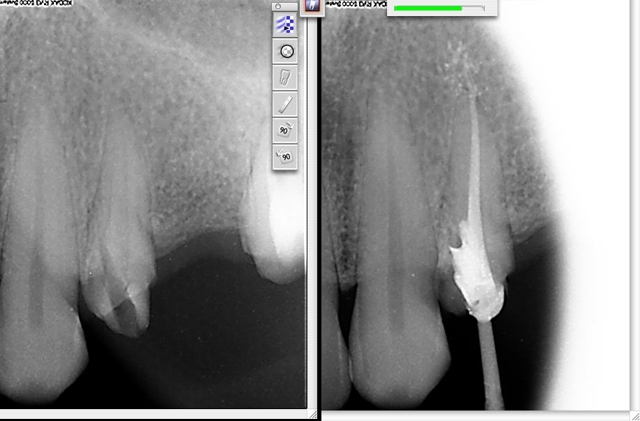

Le diagnostic est facile à faire: les perforations saignent énormément et il faut systématiquement y penser devant une hémorragie endopulpaire. La radio avec des sondes radio opaques en place confirme généralement la perforation.

Le traitement le plus simple et le plus évident est l’obturation étanche de la perforation, en évitant soigneusement les dépassements intempestifs.